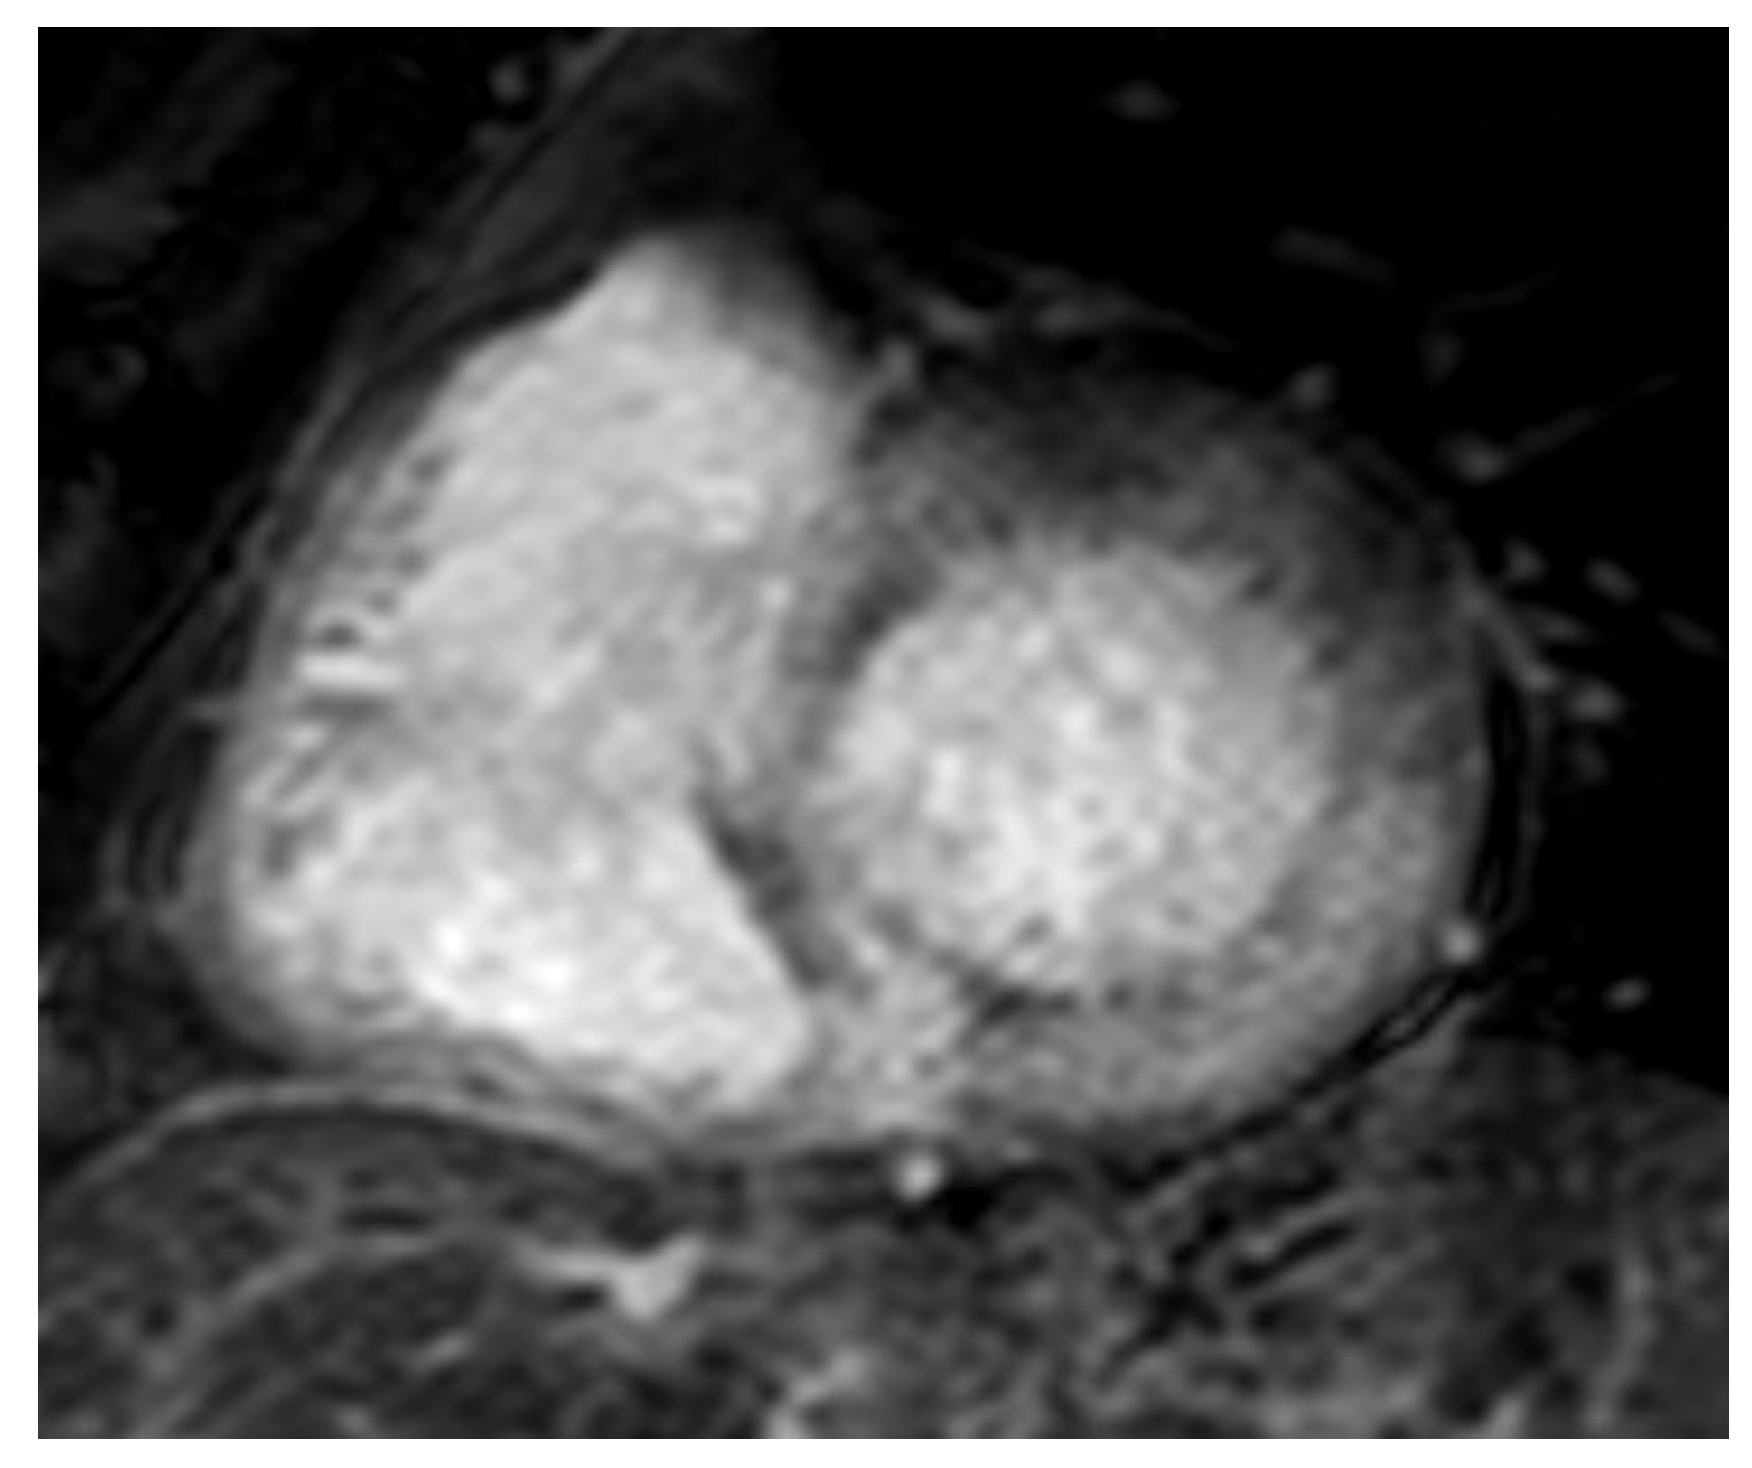

Figure 4.

AL 68-year-old patient diagnosed with endomyocardial biopsy. T1 scout sequence shows abnormal contrast agent kinetics (Dark blood pool signal).